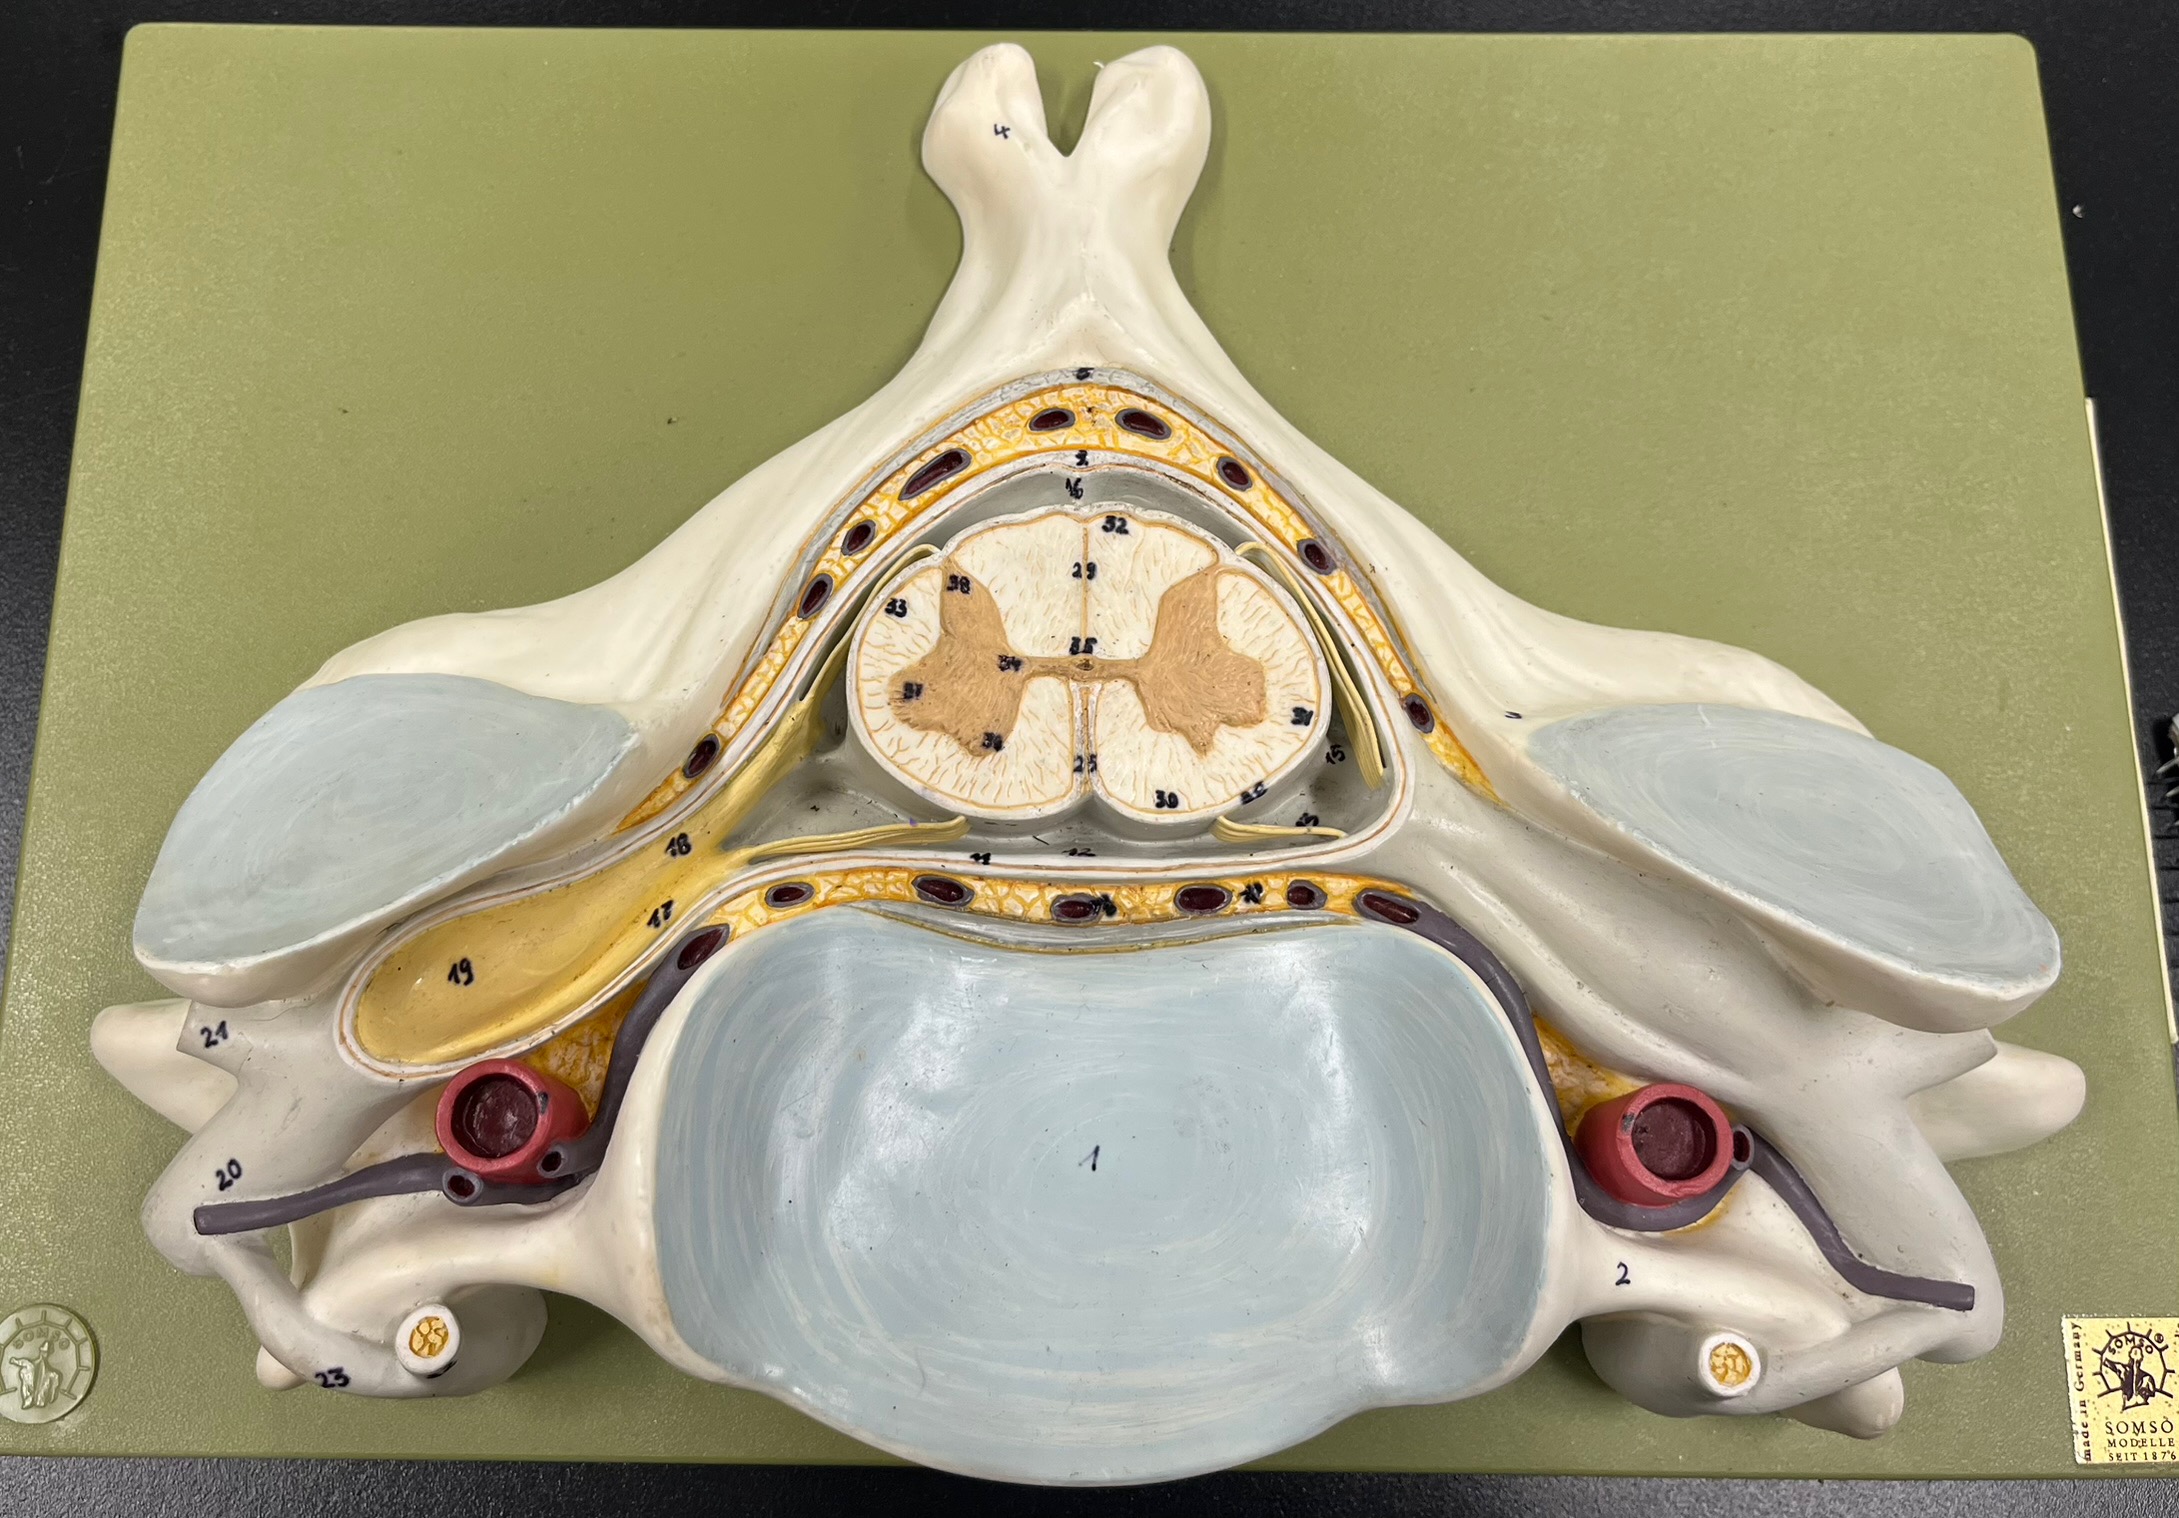

epidural space

dura mater

subdural space

arachnoid mater

subarachnoid space

pia mater

denticulate ligaments

What is the groove here?

anterior median fissure

posterior median sulcus

posterior (dorsal) horn

posterior (dorsal) horn; R—>L

anterior (ventral) horn

lateral horn (selected models)

gray commissure

central canal

anterior column

lateral column

posterior column

white commissure

posterior (dorsal) root ganglion

What is the bulb here?

posterior (dorsal) root ganglion

posterior (dorsal) root

posterior (dorsal) root

anterior (ventral) root

anterior (ventral) root

dorsal ramus

dorsal ramus

ventral ramus

ventral ramus

rami communicantes

rami communicantes

sympathetic chain ganglia

sympathetic chain ganglia